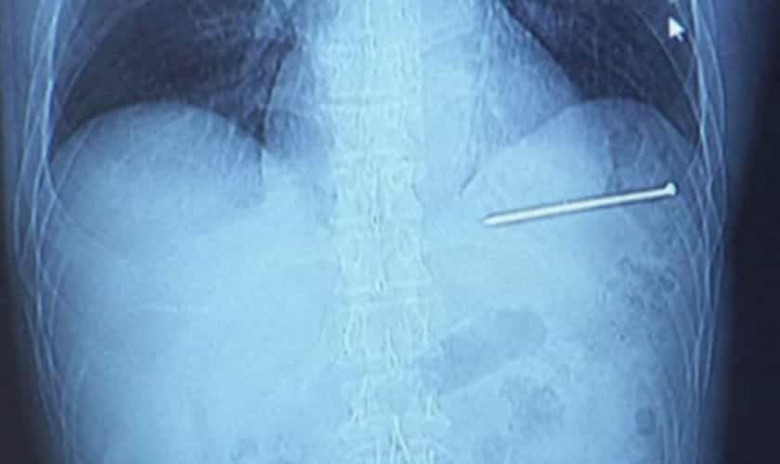

Մոտավորապես 9 սանտիմետր երկարությամբ մեխն ուղիղ մտել է նրա սիրտը, այն էլ՝ բավականին մեծ արագությամբ։

Բարեբախտաբար, մեխը չի դիպչել սրտի գլխավոր զարկերակին, սակայն մխրճվել է դրա անմիջապես կողքը՝ ընդամենը մեկ թղթի հաստության չափ հեռավորության վրա։